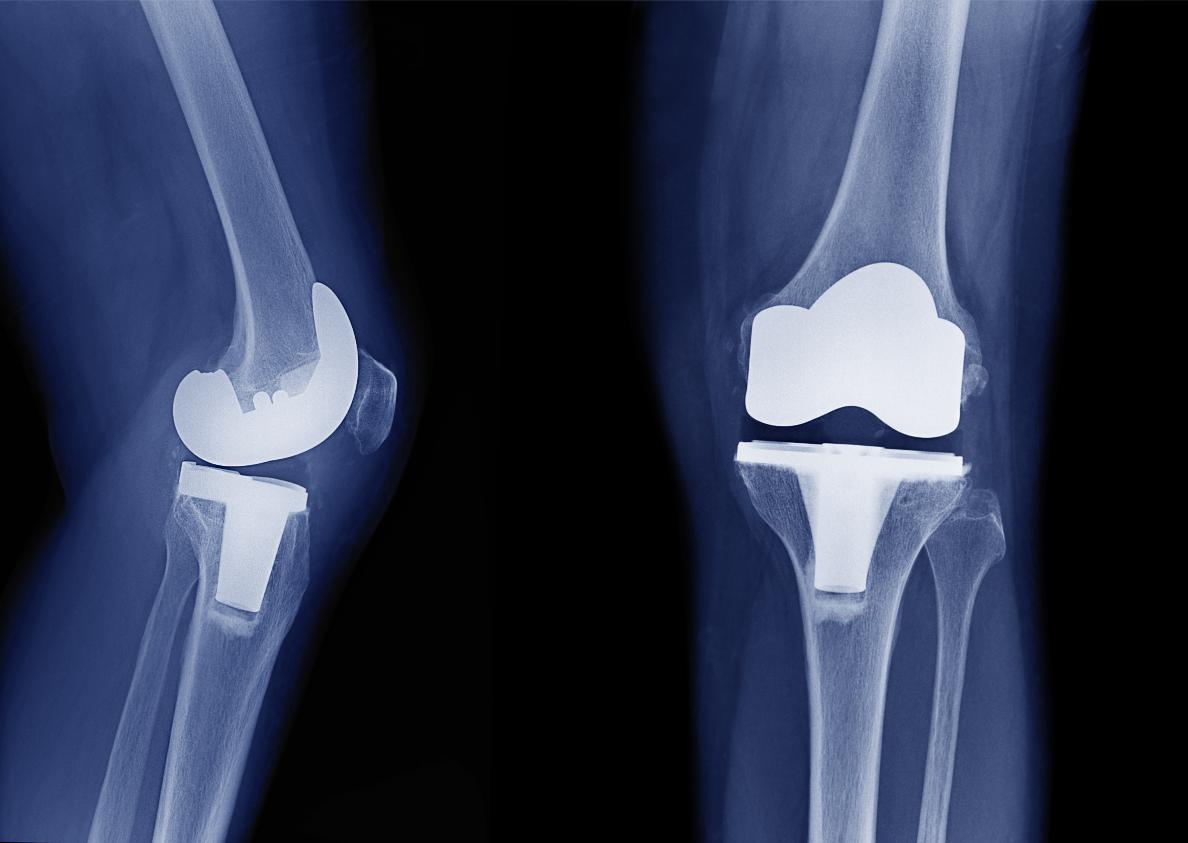

Your surgeon will use a robotic surgical arm to carry out selected parts of the procedure, especially those requiring high precision and fine movements. The robot assists the surgeon in making extremely precise cuts in your bone, helps to verify that your implants are inserted at the correct position with the best fit to your knee, and ensures that your knee is stable and optimally aligned (“straight”).